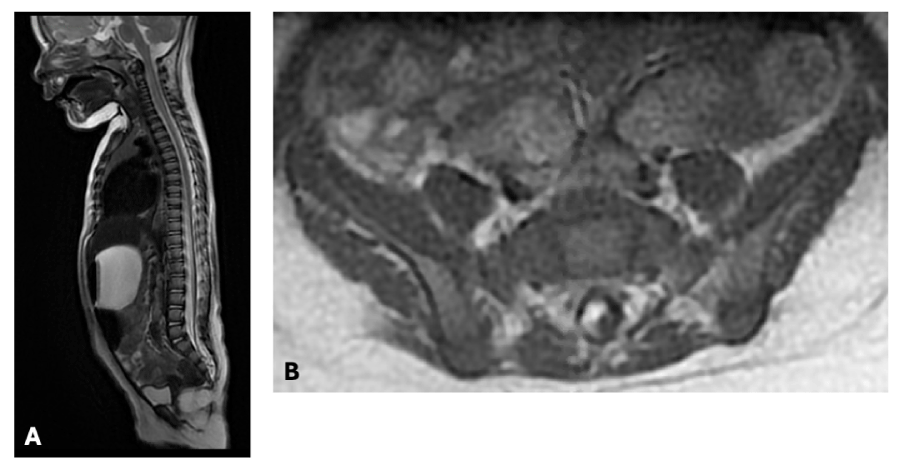

At 1 year and 4 months old, she was admitted to the emergency department for sub-acute loss of walking which had started a month earlier. She also exhibited sudden onset of urinary retention. She was thus transferred to our specialised center for management. Upon arrival, she was moving spontaneously on all-fours. She was able to stand up with support and could walk couple of steps but only with assistance. She had dorsiflexion and eversion weakness on the left greater than the right side with manual muscle testing being under 3/5. She did not respond to tactile stimulation on the left lower limb. Due to the sudden neurological deterioration cerebral and spinal MRI were ordered. The cerebral MRI was normal, and the spinal MRI was remarkable for the appearance of a large syringomyelic cavity extending from T11 to S1 with associated spinal cord edema (figure 1). She thus underwent a detethering surgery with restoration of perimedullary CSF space and near total lipoma resection. At day 1 post-surgery she had complete recovery of motor and sensory functions. Bowel and bladder resumed normal functions at day 2 post-surgery.

Figure 1: Initial radiological presentation at 7 months of age of an anterolateral trans dural transitional conus lipoma A: Sagittal T2 B: Axial T1 View Figure 1